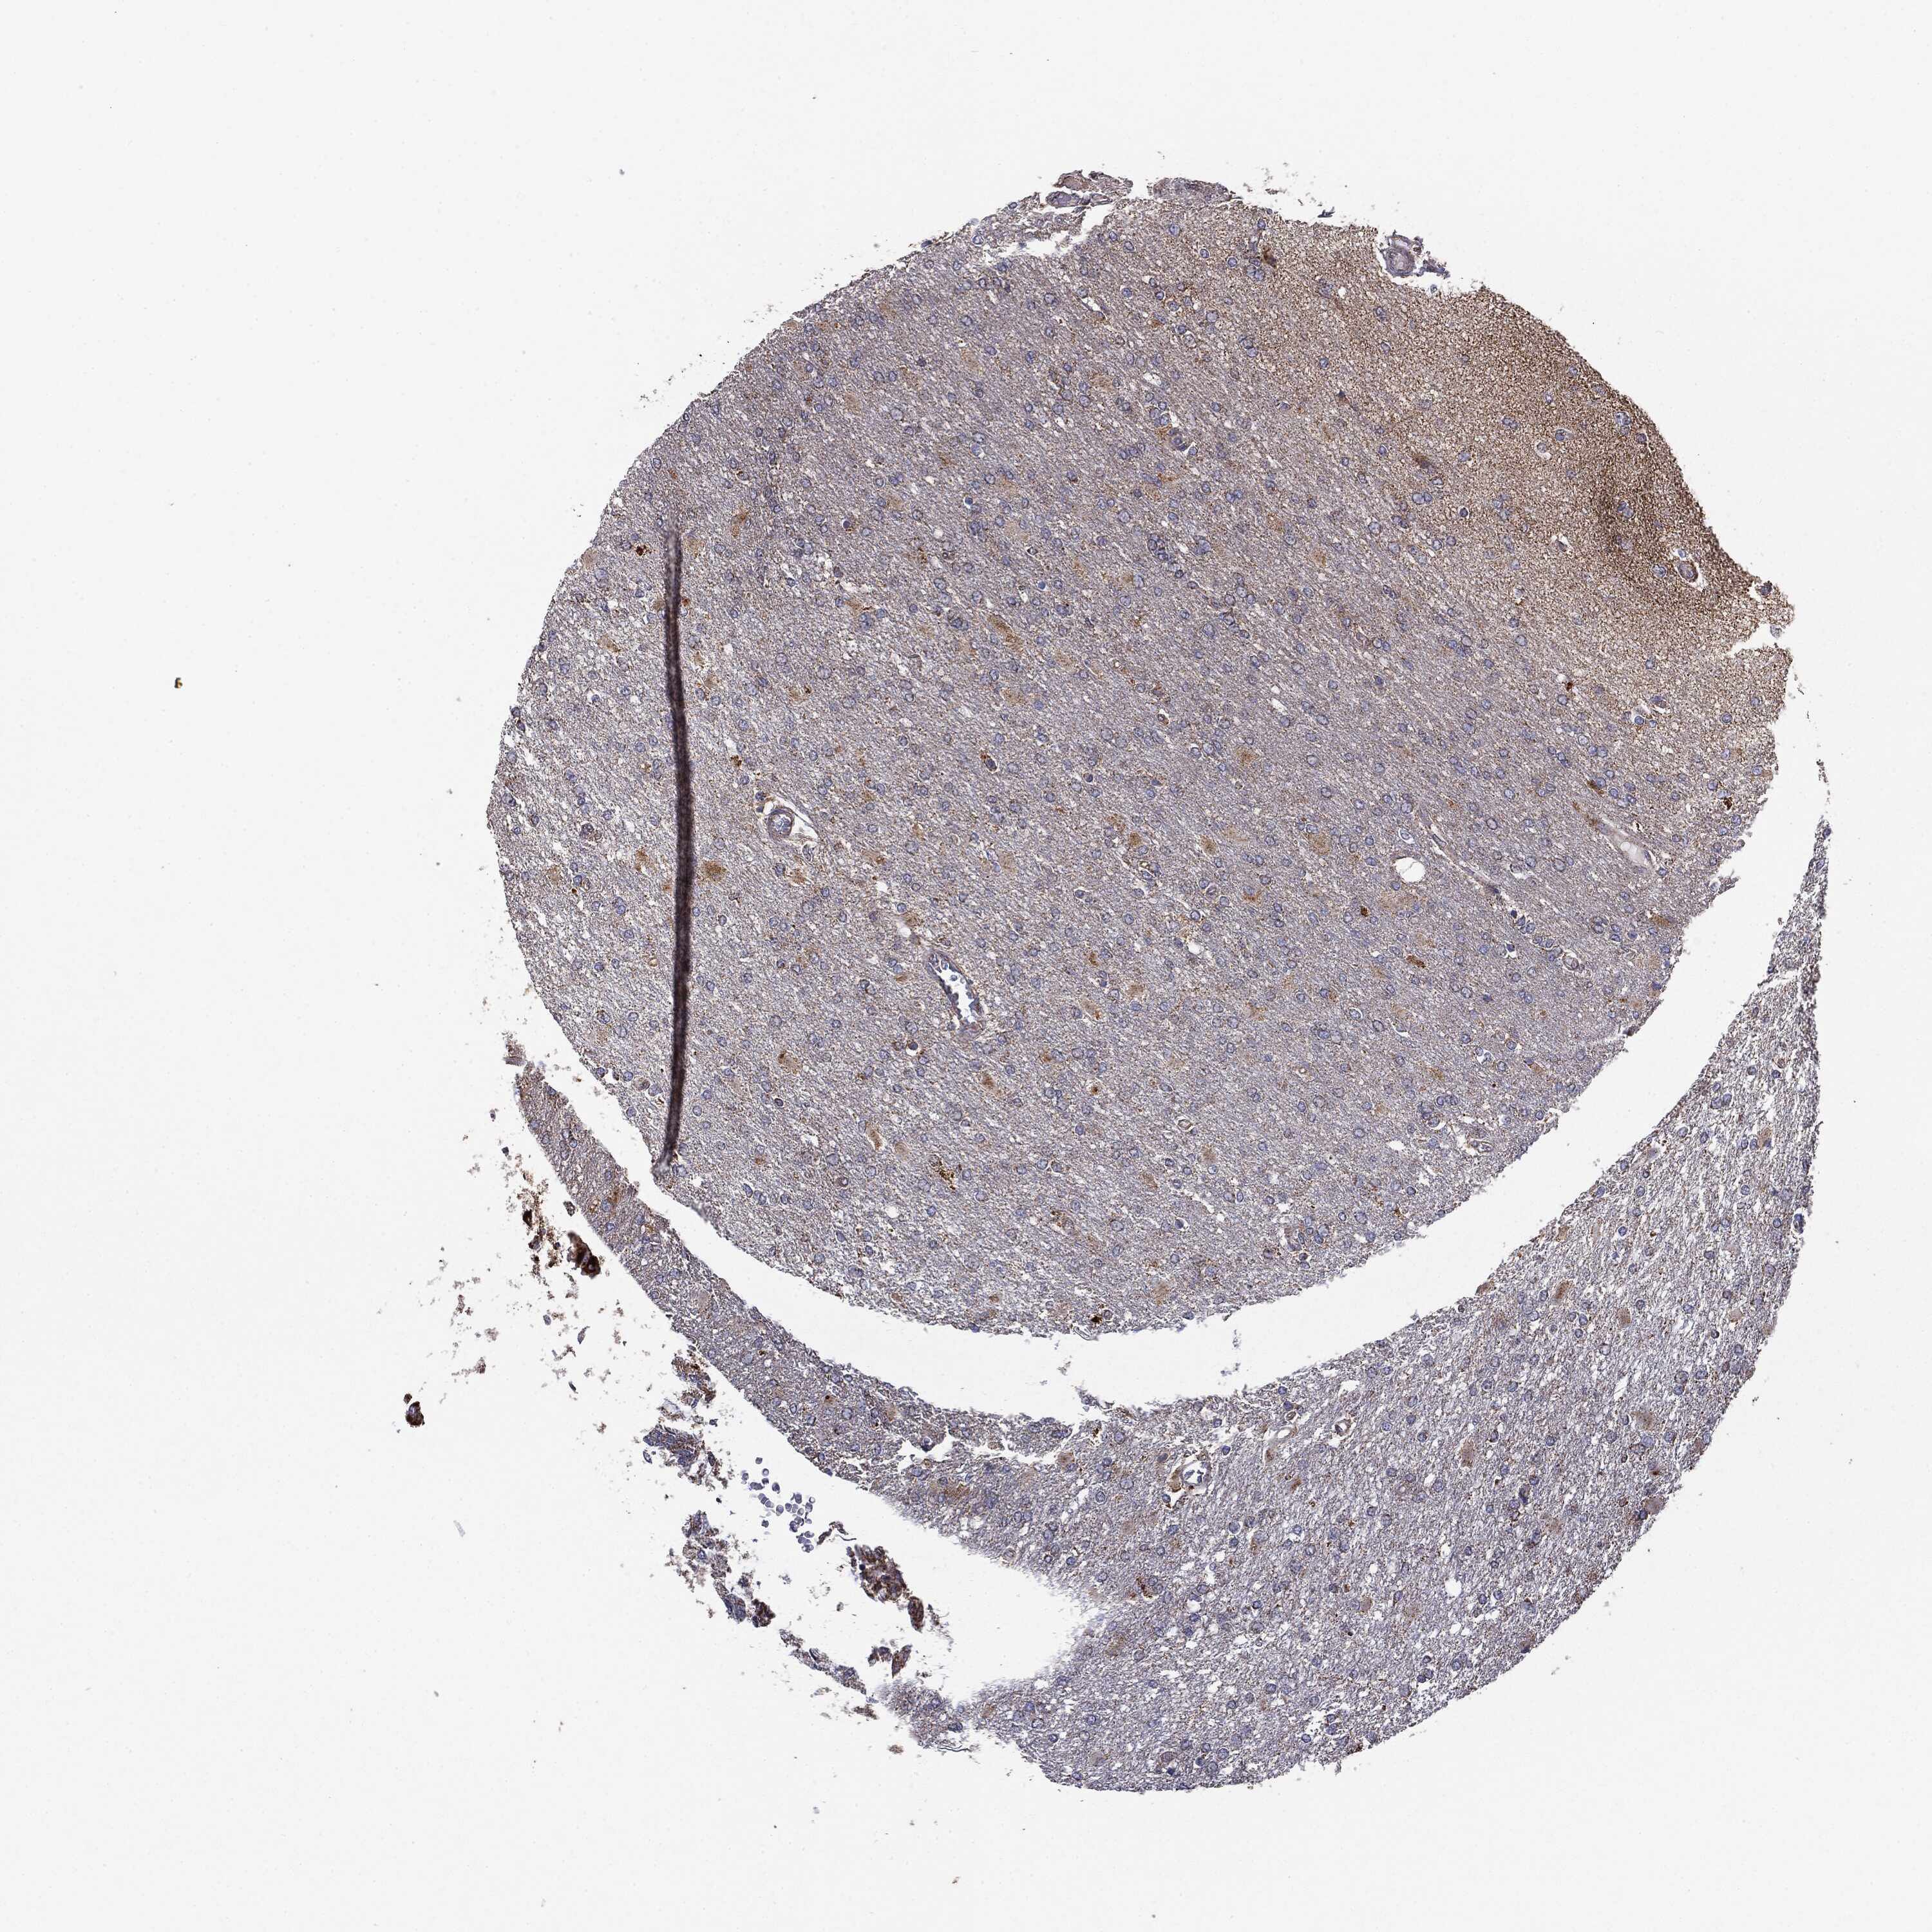

GLIOMA - Protein expressioni

A mouse-over function shows sample information and annotation data. Click on an image to view it in a full screen mode. Samples can be filtered based on level of antibody staining by selecting one or several of the following categories: high, medium, low and not detected. The assay and annotation is described here.

Note that samples used for immunohistochemistry by the Human Protein Atlas do not correspond to samples in the TCGA dataset.

Antibody stainingi

Antibody staining in the annotated cell types in the current human tissue is reported as not detected, low, medium, or high, based on conventional immunohistochemistry profiling in selected tissues. This score is based on the combination of the staining intensity and fraction of stained cells.

Each image is clickable and will lead to virtual microscopy that enables deeper exploration of all samples and also displays staining intensity scores, fraction scores and subcellular localization as well as patient and tissue information for each sample.

CAB069425

CAB080053

CAB080065

CAB080070

CAB080081

CAB080095

CAB080097

Staining

High

Medium

Low

Not detected

Intensity

Strong

Moderate

Weak

Negative

Quantity

>75%

75%-25%

<25%

None

Location

Nuclear

Cytoplasmic/membranous

Cytoplasmic/membranous,nuclear

Glioma, malignant, Low grade

Glioma, malignant, High grade

Glioma, malignant, NOS